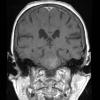

NEOPLASMS (HEMATOLYMPHOID)

Lymphoma, secondary (9)